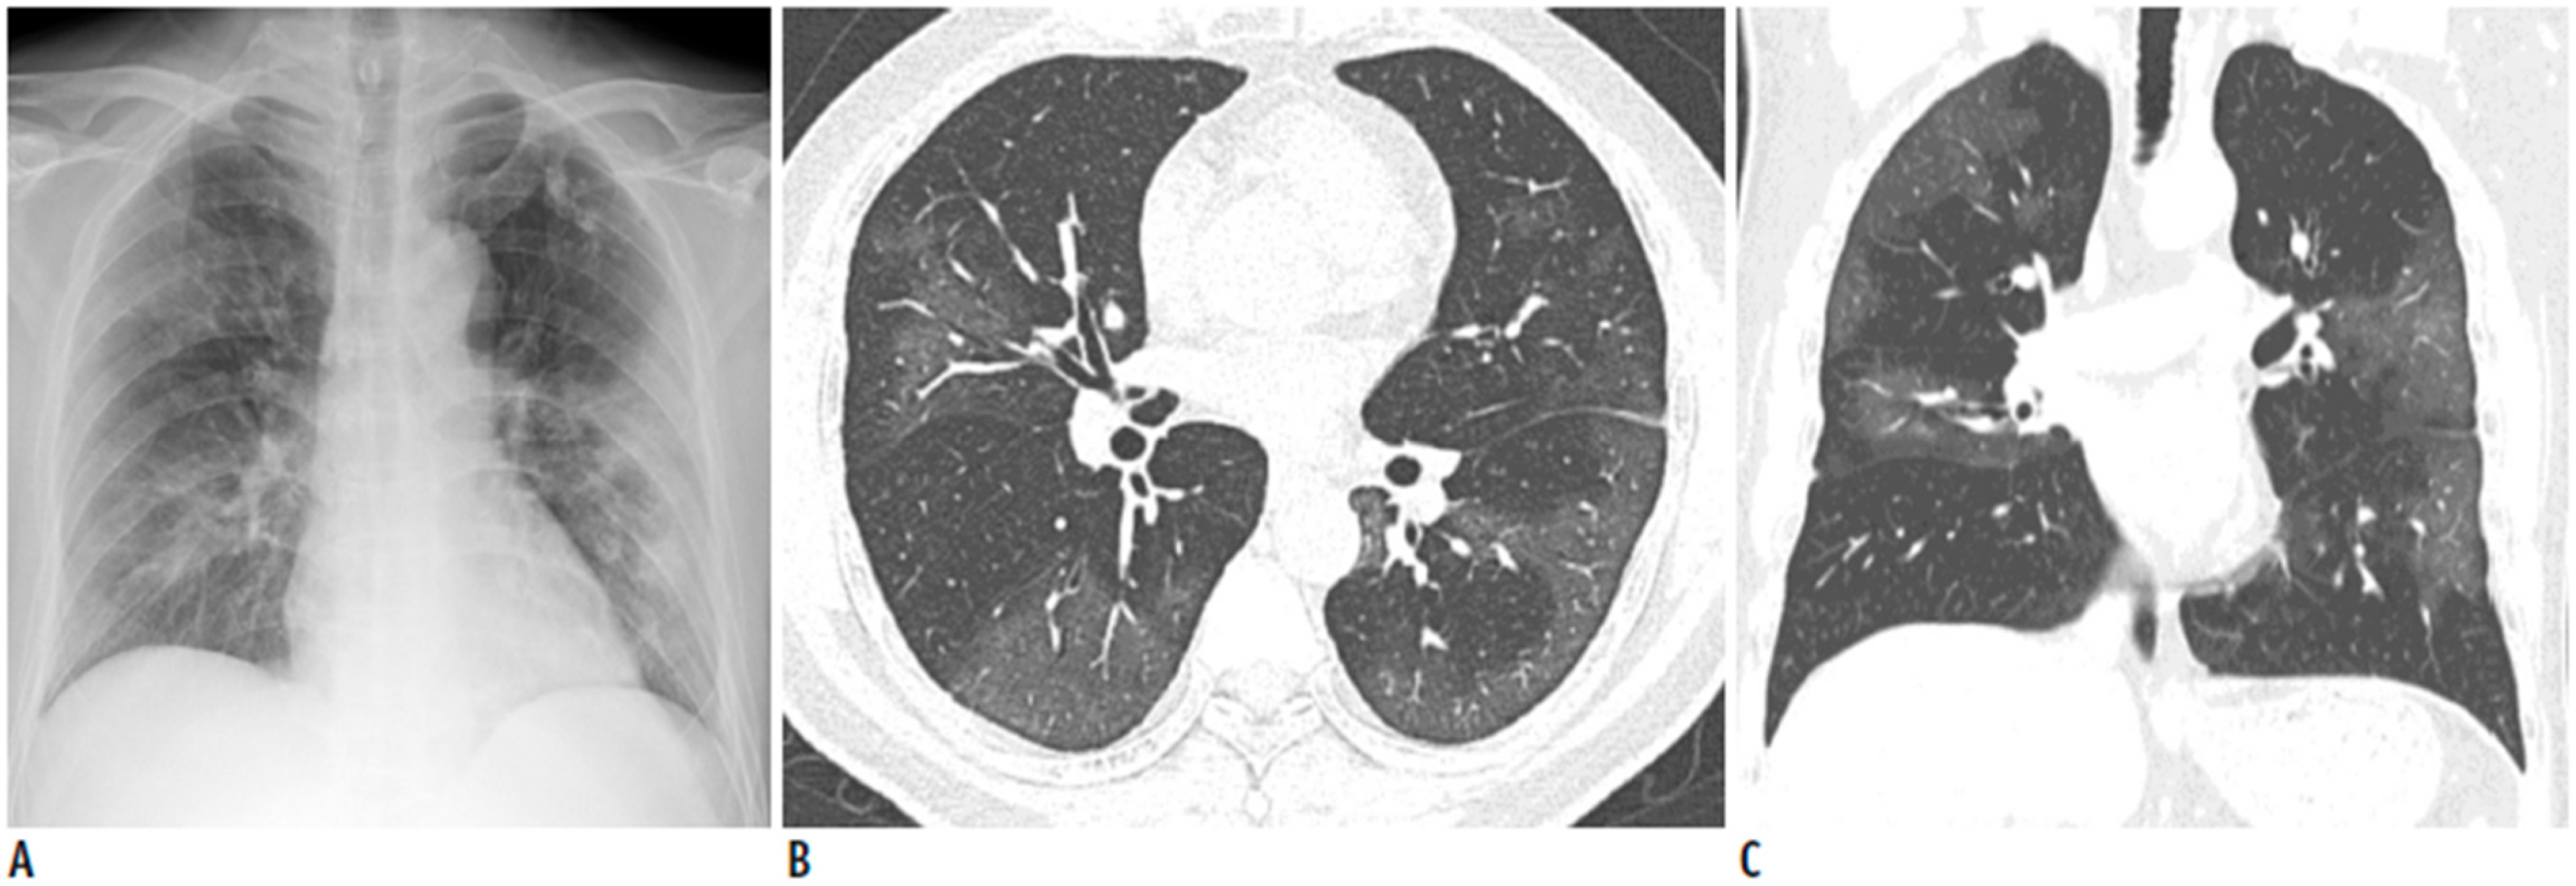

3.1. Case A